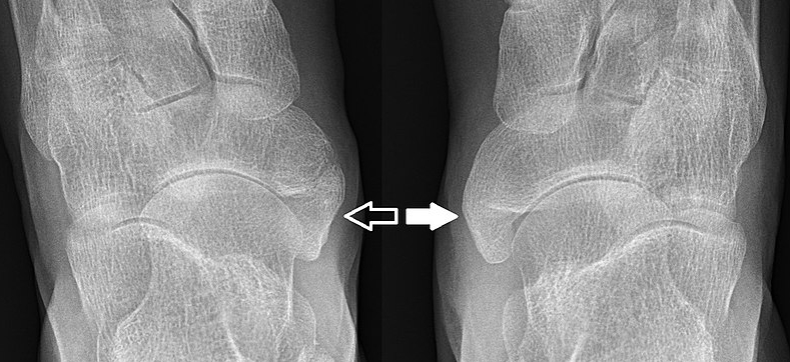

닥터 구글과 함께 탐정 놀이를 하고 싶은 유혹이 있지만, 이런 상황에서는 실제 의료 전문가가 최고의 조력자입니다. 의료진은 엑스레이나 MRI와 같은 검사를 통해 내비경이 문제인지 확인할 수 있습니다.

이러한 검사는 고통스럽지 않으며 의사가 표면 아래에서 무슨 일이 일어나고 있는지 확인하는 데 도움이 되니 걱정하지 마세요.

- 상담 및 서류 작성: 보험 절차를 시작하려면 종합적인 평가를 위해 의료 전문가와 상담해야 합니다. 병력, 신체 검사 결과, 엑스레이 또는 MRI와 같은 진단 영상에 대한 문서화는 부주상골 증후군의 존재와 중증도를 입증하는 데 중요한 역할을 합니다. 이러한 기록은 보험 청구의 기초가 됩니다.